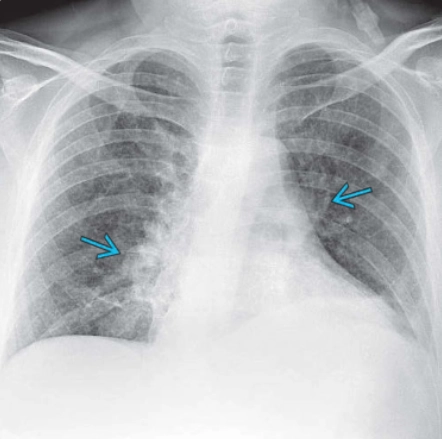

Tổn thương phổi liên quan đến sử dụng thuốc lá điện tử hoặc sản phẩm vaping (E-cigarette or vaping product use-associated lung injury - EVALI)